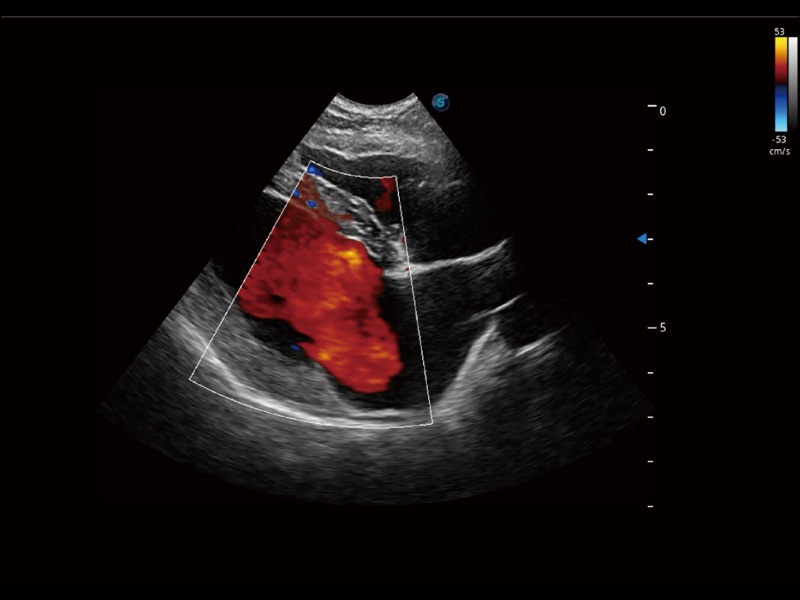

采用红、橙、黄、绿、青、蓝、紫这七种肉眼最为敏感的色彩,直观地显示组织内血流灌注的时间先后信息,更精准捕捉血流灌注走行细节。

通过色彩血流和实时宽景相结合,可观察到完整的静脉或动脉的血流,方便医生检查。实时扫查过程中,如有任何操作失误也可以很容易地进行回扫擦除,而不会中断扫查。